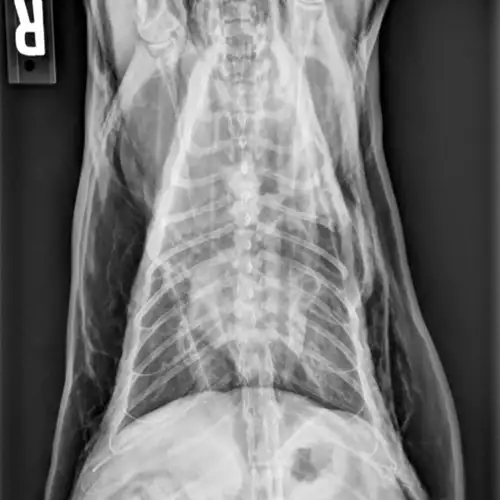

Figure 1 Radiographic image of a cat with a tracheal tear and severe subcutaneous emphysema

Radiography can be used to diagnose tracheal tears (Figures 1 and 2). If a tracheal tear is present, thoracic radiographs may reveal pneumomediastinum, subcutaneous emphysema, pneumoretroperitoneum, hyperinflated lung fields, a gas-filled pseudo-airway at the level of the rupture, focal narrowing of the tracheal lumen, and/or pneumothorax if the mediastinum has been perforated due to air pressure.3